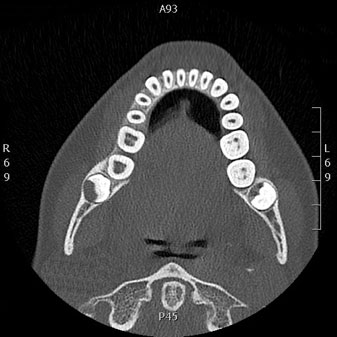

Tomografía computarizada Maxilar y Mandibular

Está indicado para el estudio implantológico, de extracciones dentales o valoración de patología en el hueso del maxilar superior e inferior.

Ejemplos